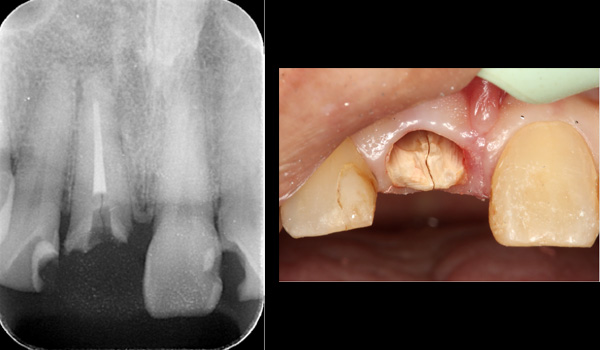

| 年代・性別 | 30代 男性 |

|---|---|

| 主訴 | 前歯が腫れた |

| 治療期間 | 約18ヶ月 |

| 費用 | 700,000円 |

| 治療内容 | インプラント、部分矯正、骨造成、結合組織移植、セラミック修復 |

| 治療に伴うリスク | インプラント周囲炎 セラミックの破折、脱離 |

*キャンセルポリシーをご一読のうえご予約ください